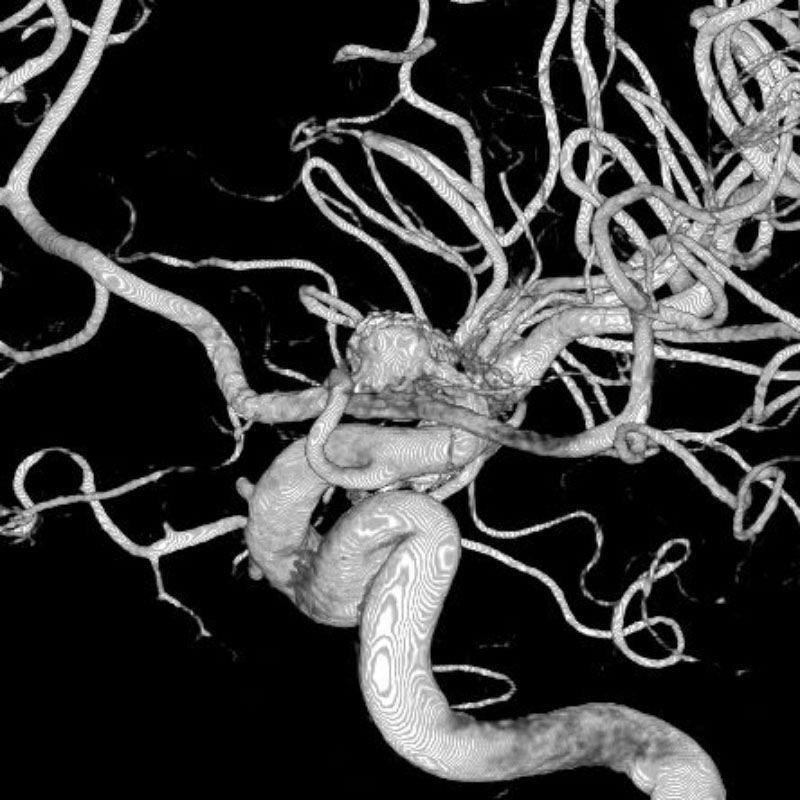

脳動静脈奇形

血管塞栓術

芝野/古谷